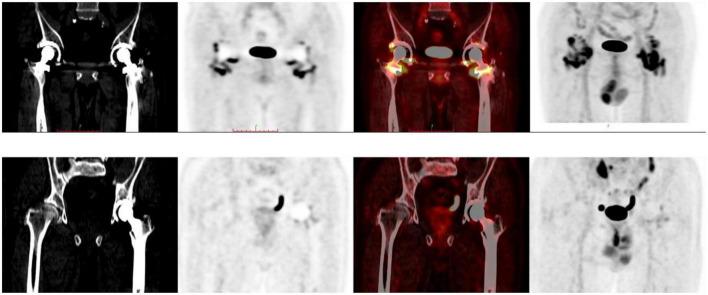

The aim of this study was to retrospectively analyze 18F-fluorodeoxyglucose (F-FDG) positron emission tomography (PET)/ computed tomography (CT) images of non-infected hip arthroplasty patients and summarize findings that may be useful for clinical practice.

F-FDG PET/CT images of non-infected hip arthroplasty patients were collected from September 2009 to August 2021. The region of interest was independently delineated by two physicians and maximum standardized uptake values (SUV) were recorded and compared. Serologic data were also collected and the correlation between SUV and serologic parameters was analyzed, while the images were classified based on the F-FDG uptake pattern in the images using the diagnostic criteria proposed by Reinartz et al. (9). The interval between hip replacement and PET/CT was classified by year and the characteristics of the two groups were compared. The images of patients who underwent PET/CT multiple times were analyzed dynamically.

A total of 121 examinations were included; six patients underwent PET/CT twice and two patients had three scans. There were no significant correlations between SUV and serologic results. The interobserver agreement between the two physicians in the classification according to the criteria of Reinartz et al. (9) was 0.957 ( < 0.005). Although there was non-specific uptake in cases with an arthroplasty-to-PET/CT interval this was non-significant. Additionally, F-FDG showed potential utility for dynamic observation of the condition of the hip.

SUV provided information independent of serologic results, meanwhile F-FDG showed potential applicability to the dynamic monitoring of hip arthroplasty-related diseases. However, the presence of blood vessels and muscles affected image interpretation and the specificity of F-FDG was not optimal. A more specific radionuclide is needed to maximize the benefits of using PET/CT for the assessment of periprosthetic joint infection (PJI).